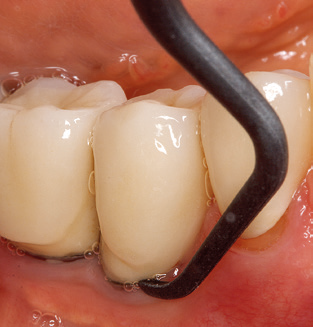

Fig. 4: Flexible probes with millimetre markings are recommended for the probing of dental implants (e.g. Colorvue Kit PCV11KIT6, Hu­Friedy). – Fig. 5a and b: A straight working tip (1P, W&H Dentalwerk Bürmoos GmbH) is a suitable instrument for use on all natural teeth. – Fig. 6: Curved working tips (3Pr/3Pl, W&H Dentalwerk Bürmoos GmbH) lend themselves to the processing of difficult-to-reach areas of the tooth and root surfaces (e.g. furcations). – Fig. 7: The tapered, hexagonal implant cleaning tip (1I, W&H Dentalwerk Bürmoos GmbH) permits atraumatic and efficient cleaning of the crown and abutment surfaces. – Fig. 8: Titanium and carbon curettes are suitable instruments for the manual cleaning of the implant surfaces.

Of course, working tips for the cleaning of implant surfaces are also indispensable for SPT in patients fitted with implants. The implant cleaning attachment on the system used here is characterised by its tapered, hexagonal design. This design allows light, atraumatic penetration of the peri-implant pocket and displays a good cleaning performance (Fig. 7).